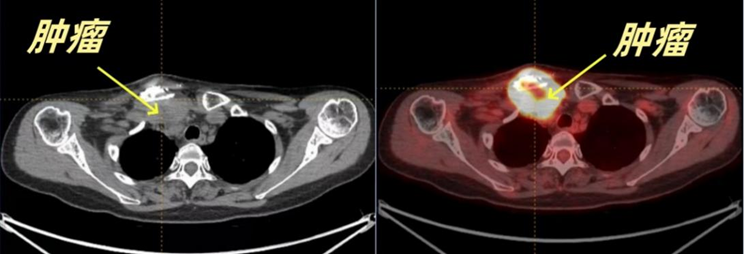

因肿瘤位于骨骼处,李女士慕名来到附属第六人民医院胸外科杨异主任专家门诊就诊。棘手的是,肿瘤已经长到鸡蛋样大小了。入院进一步检查发现,肿瘤位于右侧胸锁关节、右侧第一肋骨,不仅突出体外,而且向颈部深处生长,侵犯右侧甲状腺,压迫血管造成颈内静脉血栓;同时肿瘤又向纵隔内生长,逼近纵隔内的大血管。面对这种罕见而复杂的情况,治疗方案的制定变得异常困难:若行手术,可能无法彻底切除,或者彻底切除后脏器功能损害,生活质量下降,影响后续内科治疗;但如果不手术,由于没有明确的病理类型,不能有的放矢地制定治疗方案。即便患者进行内科辅助治疗,治疗效果也将大打折扣,从而影响生存,同时患者也将面临着肿瘤继续增大而破裂流脓、甚至出现转移而威胁生命的风险。